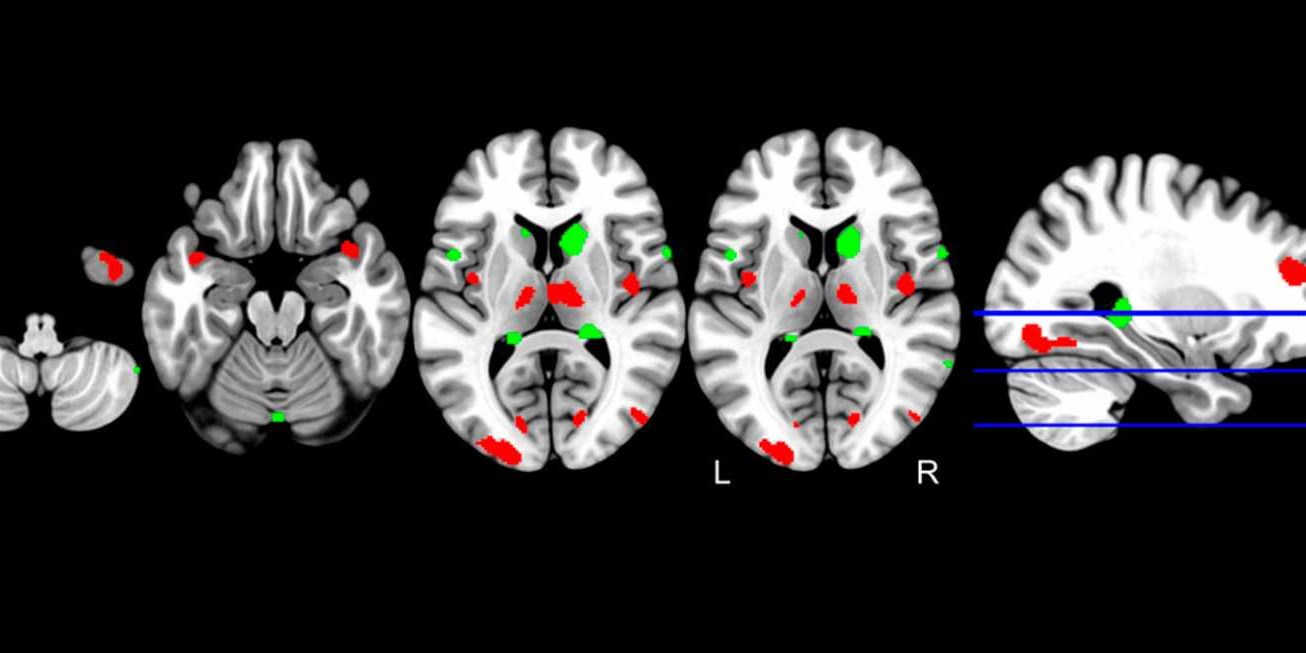

El cerebro de quien desarrollará alzhéimer es genéticamente distinto https://t.co/LOBUwUx3uq